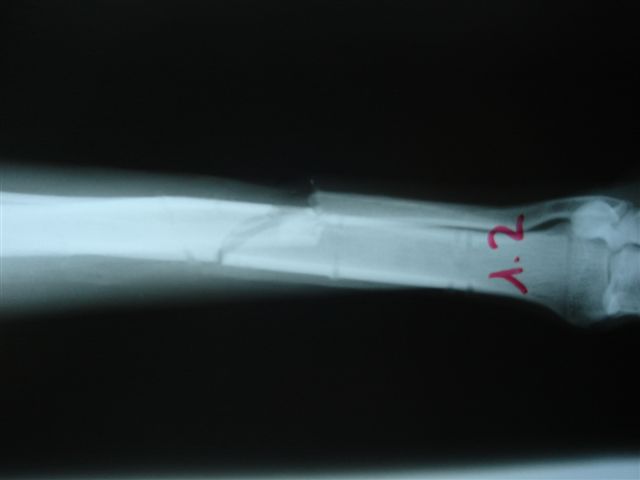

Fijación Externa en IVOT

Fijación Externa

IX CURSO BASICO DE FIJACION EXTERNA.

Casos prácticos alumnos.